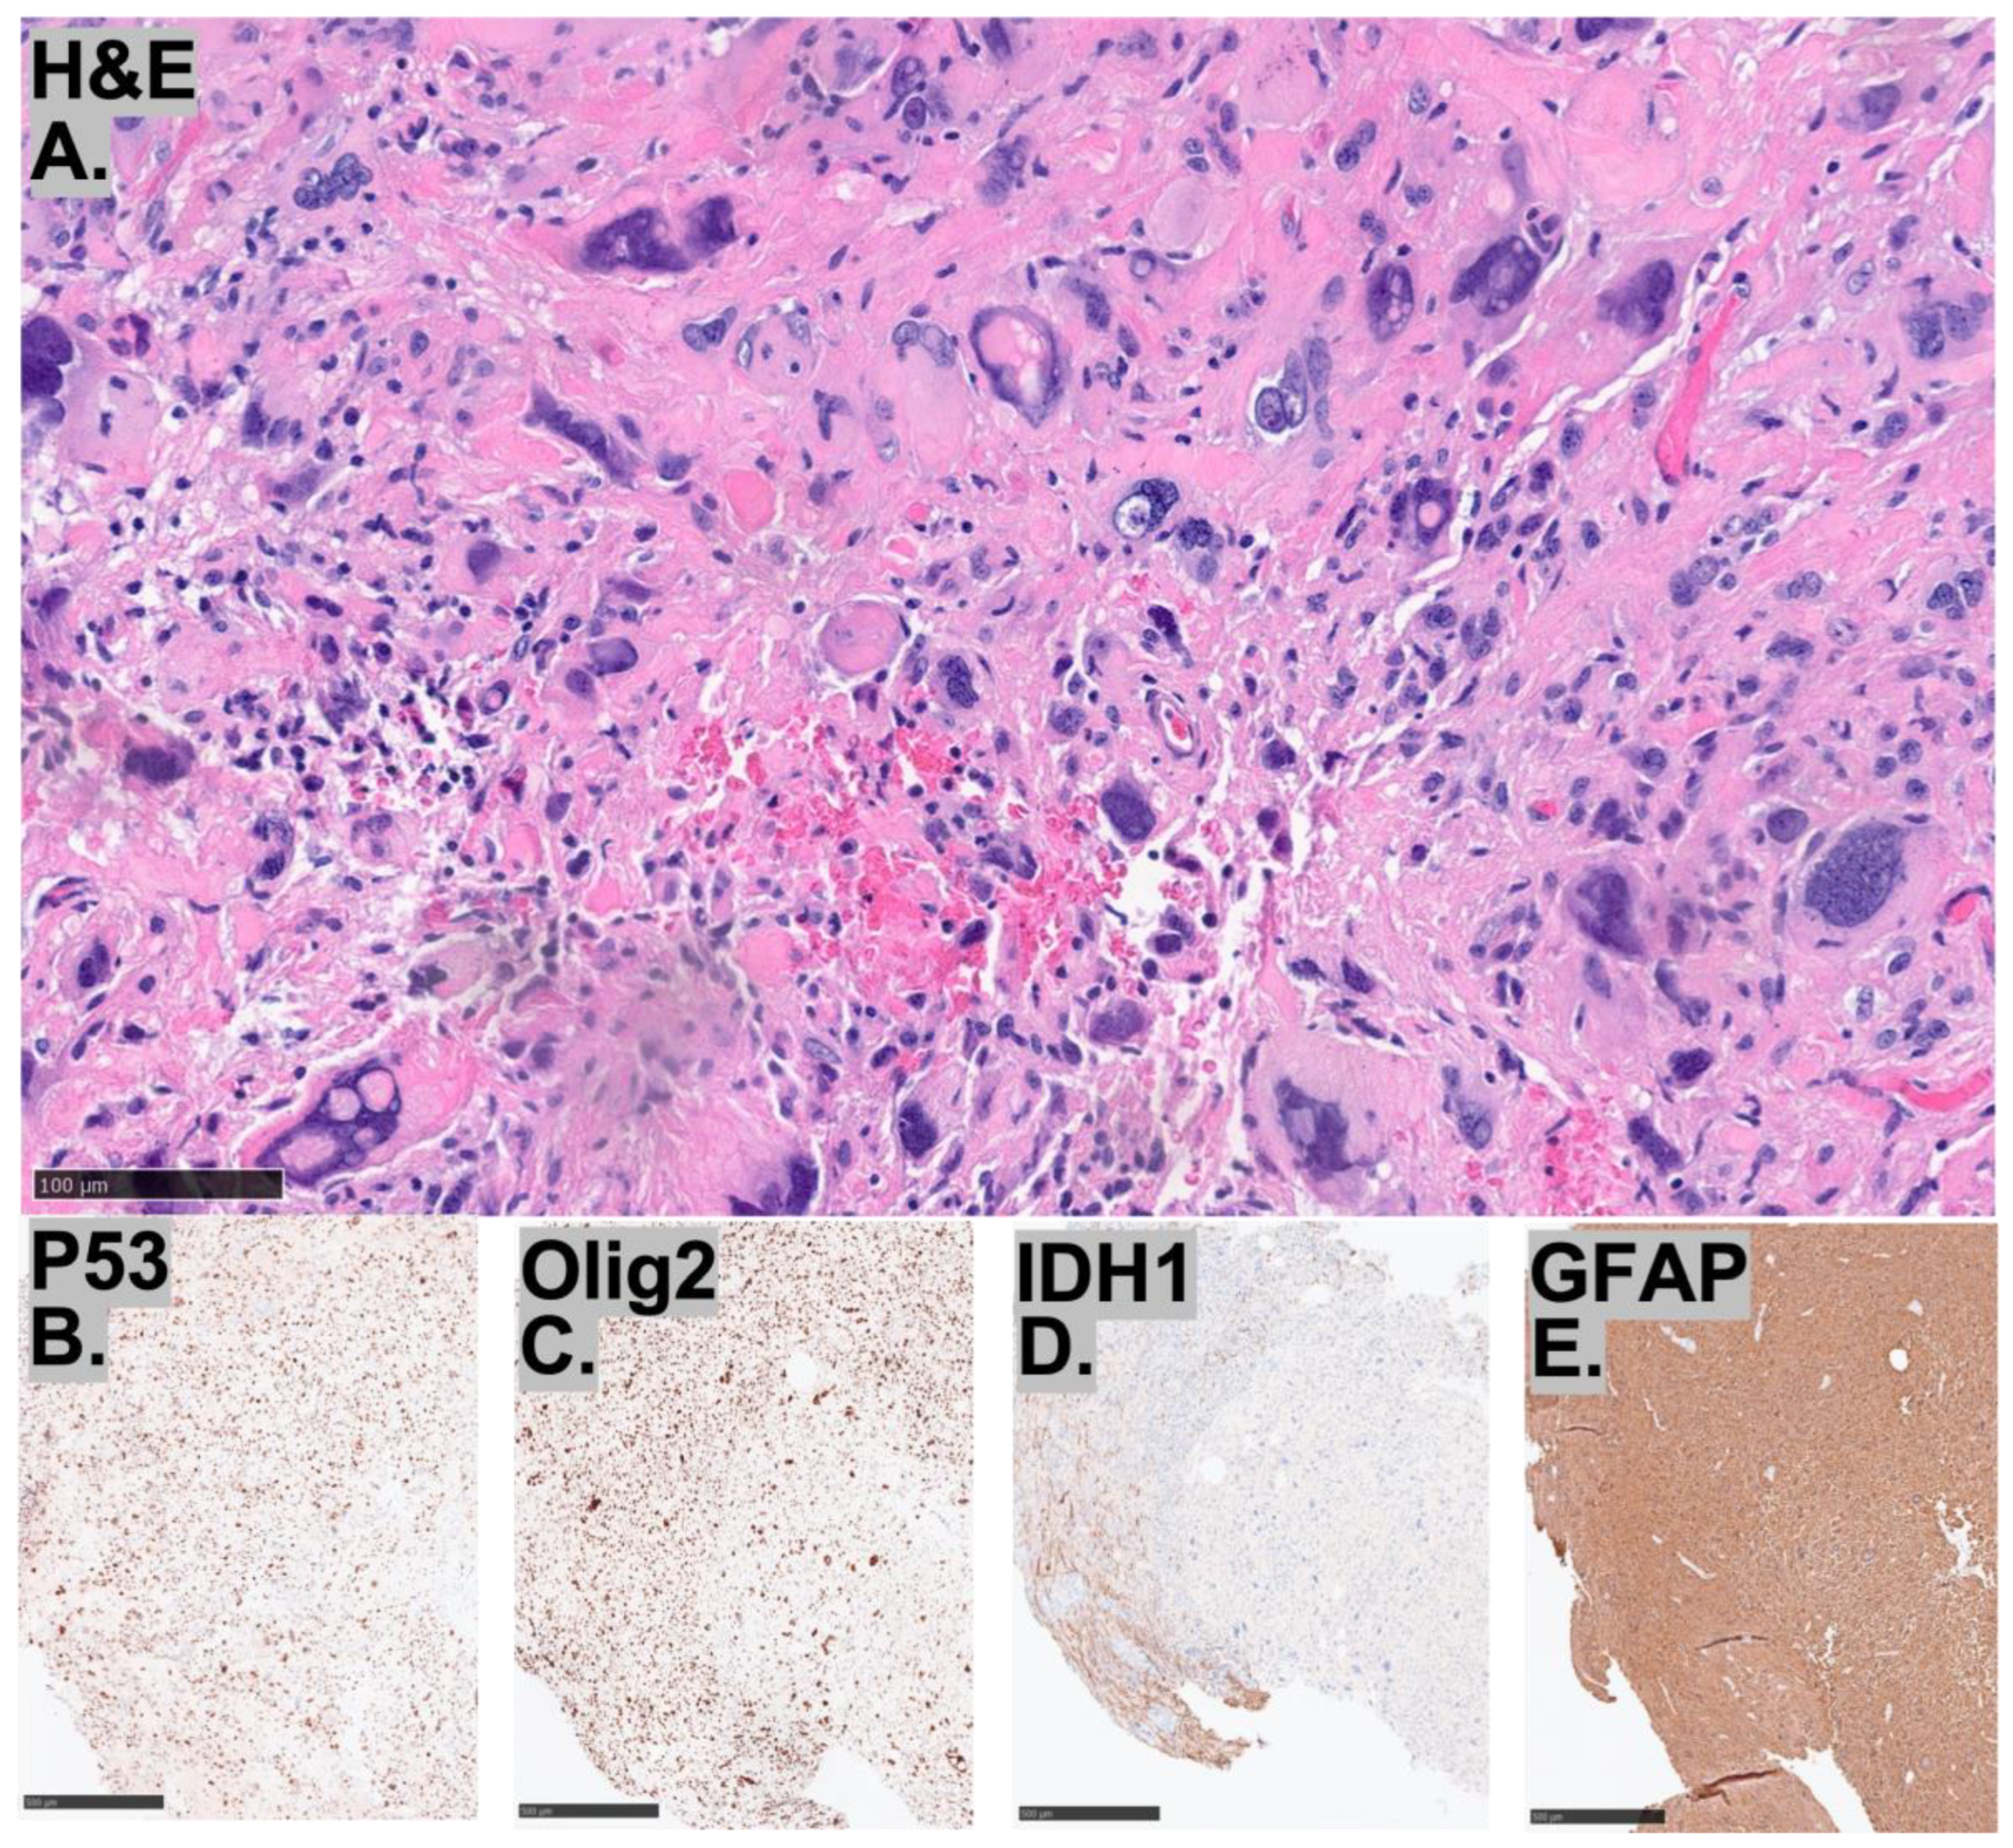

2.3. Histopathological Characteristics of the Tumors

2.4. Molecular Characteristics of the Tumors

| Histopathology | Case 1 | Case 2 | Case 3 |

|---|---|---|---|

| ATRX | + | + | + |

| p53 | overexpression | overexpression | overexpression |

| Ki-67 index | elevated | elevated | elevated |

| IDH1 | − | − | − |

| GFAP | + | + | + |

| Synaptophysin | weakly positive | ||

| Olig2 | − | patchy positivity | + |

| BRAF V600E | − | − | |

| H3K27M | − |